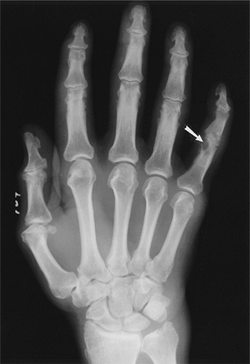

![]() |

FIGURE 13-26 Gout. Swelling of the right hand and wrist with a well-defined erosion (arrow) at the fifth PIP joint.